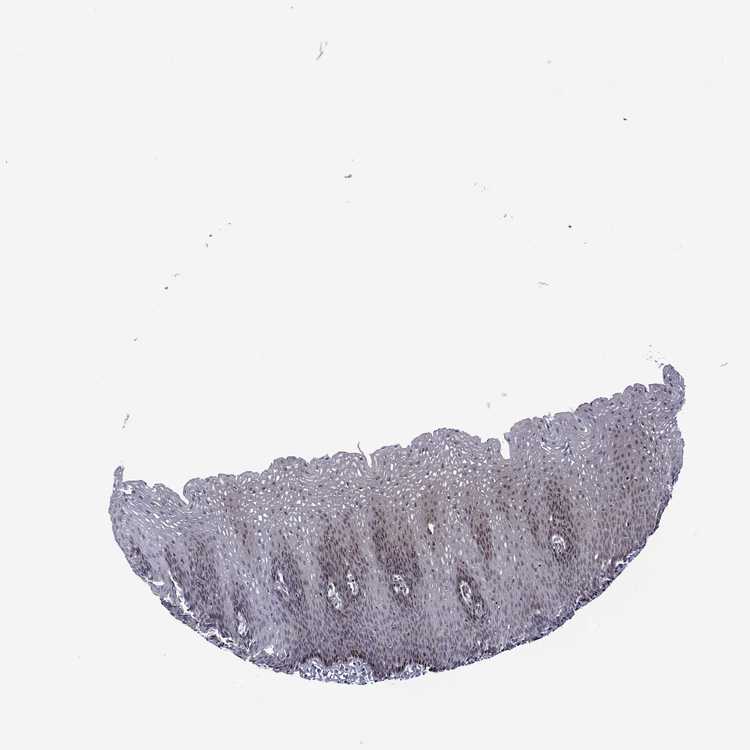

ESOPHAGUS - Antibody stainingi

Antibody staining in the annotated cell types in the current human tissue is reported as not detected, low, medium, or high, based on conventional immunohistochemistry profiling in selected tissues. This score is based on the combination of the staining intensity and fraction of stained cells.

Each image is clickable and will lead to virtual microscopy that enables deeper exploration of all samples and also displays staining intensity scores, fraction scores and subcellular localization as well as patient and tissue information for each sample.

Antibody HPA075545

Squamous epithelial cells Not detected